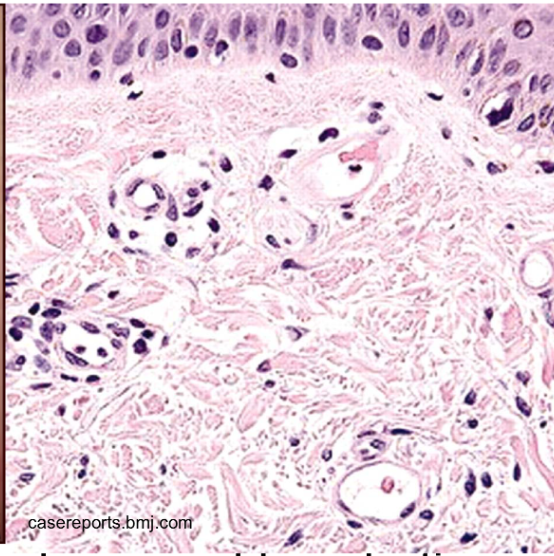

Suprabasal acantholytic blister histology

row of tombstones, intact basal cells at base of blister

pemphigus vulgaris

Portion of epidermis (including stratum corneum) forms the roof of bullae